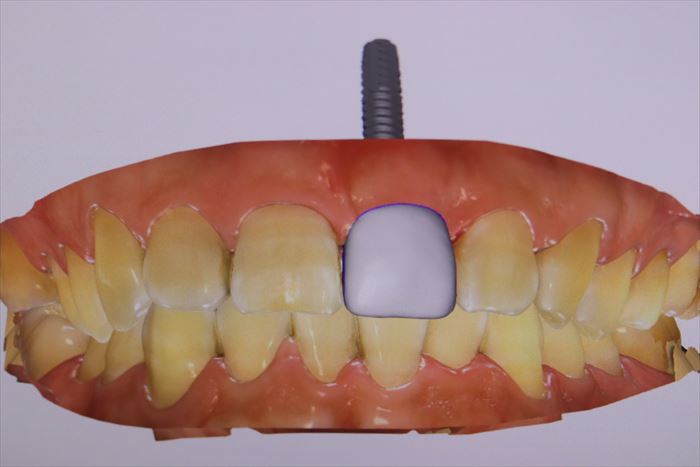

セレックプライムスキャンでジルコニアカスタムアバットメントとレジン製の仮歯を製作します。

左端のインプラントアナログ(インプラントの接続部分を模したもの)にこのように接続します。